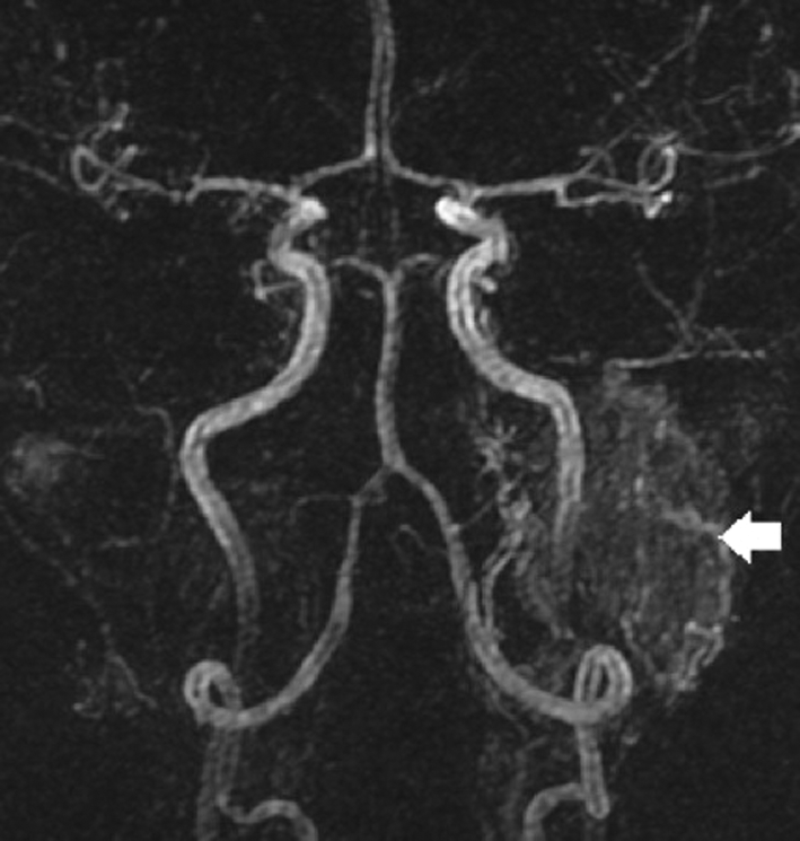

Patients with pulsatile tinnitus and no otoscopic abnormality, may be imaged with either CT or MRI based protocols. The studies should be specifically directed at the likely vascular pathologies, and each imaging department should have a ‘pulsatile tinnitus protocol’ in place. CT studies should be enhanced with a contrast bolus timed to opacify both arterial and venous compartments (combined CTA / CTV), with the coverage extending from the carotid bifurcation inferiorly to the vertex superiorly. MRI studies should include gadolinium enhanced thin section sequences through the skull base, together with MR arterial (MRA) and MR venous (MRV) sequences. In patients with arterial tinnitus, these MRI or CT based protocols should be systematically analysed for the principle differential diagnoses of vascular malformations (in particular dural arterio-venous fistulae), arteriopathies and vascular neoplasms (Figure 2).

Furthermore, the development of time-resolved MRA studies (Figure 2), which repeatedly capture data over time in order to depict vascular dynamics, will also improve the non invasive assessment of intracranial arterial venous shunting [12]. In patients with venous tinnitus, the primary diagnostic considerations are of idiopathic intracranial hypertension and venous variants. Severe bilateral transverse sinus stenoses, as demonstrated on the MRV / CTV studies, are highly suggestive of idiopathic intracranial hypertension and should prompt neuro-ophthalmology referral. There are also various skull base venous anatomical variants such as high riding jugular bulbs, jugular bulb diverticula, large emissary veins and lateralised sigmoid sinuses, which have been associated with venous pulsatile tinnitus. However these variants are common and it is frequently difficult to determine a direct causal relationship.

Figure 2: Selected image from arterial phase of a time resolved gadolinium

enhanced MRA study demonstrates left glomus jugular tumour (arrow).